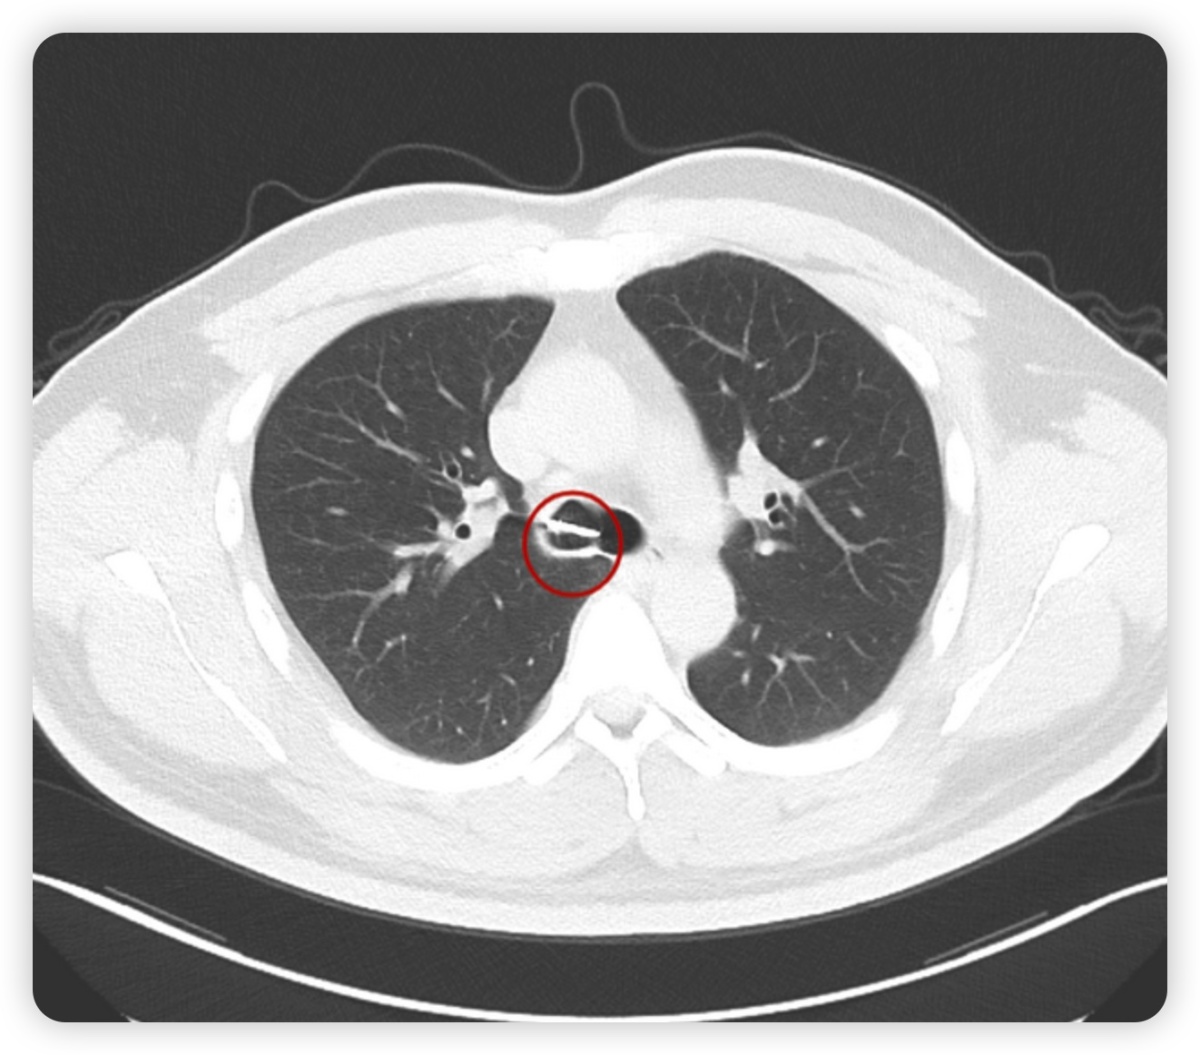

经检查,患者胸部CT提示右主支气管腔内见一“π”形高密度影,横径约18.9mm,长径约19.6mm,短径约8.0mm。

为避免气管镜操作时刺激患者剧烈咳嗽,内镜诊疗部刘薇医师及武秋菊主管护师在术前为患者进行局部麻醉,术中发现一“π”形异物卡顿于气管隆突及右主管口处,异物质地硬,似金属物,表面光滑,若贸然硬取可能会划伤患者支气管粘膜,在不断地调整角度后开始钳夹异物,气管镜缓慢移动并经过声门,最后将异物顺利取出。